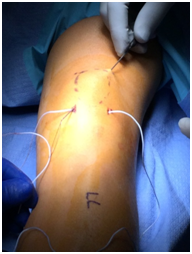

Four small incisions were made, each measuring 3-5mm. Two on either side of the proximal patella tendon or two more on either side of the distal quadriceps tendon. Labeled 1-4 (Figure 2). A large straight Keith needle was used to pass the suture starting from point 1 to 2, through the patella tendon at the inferior pole of the patella (Figure 3). The free suture end from point 2 is subcutaneously retrieved to point 3 with a Hewson suture passer (Smith and Nephew, Andover MA) (Figure 4). This free end of this suture is then passed from point 3 to 4 is with a straight Keith needle, through the quadriceps tendon at the superior pole of the patella. Finally, the other free suture end is retrieved from point 1 and delivered to point 4 (Figure 5). The free suture ends are then tensioned and tied at point 4 (Figure 6), completing the figure-of-8 tension band. A small tenotomy scissor was placed into each of the four incisions freeing the bursa from the tension band suture. Once all skin adhesions were clearly released, the four small incisions were closed, each with a single nylon suture.

Figure 5 Keith needle placing the retrieved suture through the distal quadriceps tendon, point 3 to 4.

Figure 6 Hewson suture passer subcutaneous retrieval of the free suture at the patella tendon, point 1 and deliver to the quadriceps tendon, at point 4.

Figure 7 Sutures ready to tension and tie at point 4 with figure-of-8 tension band complete. All adhesions released through each of the four small incisions.